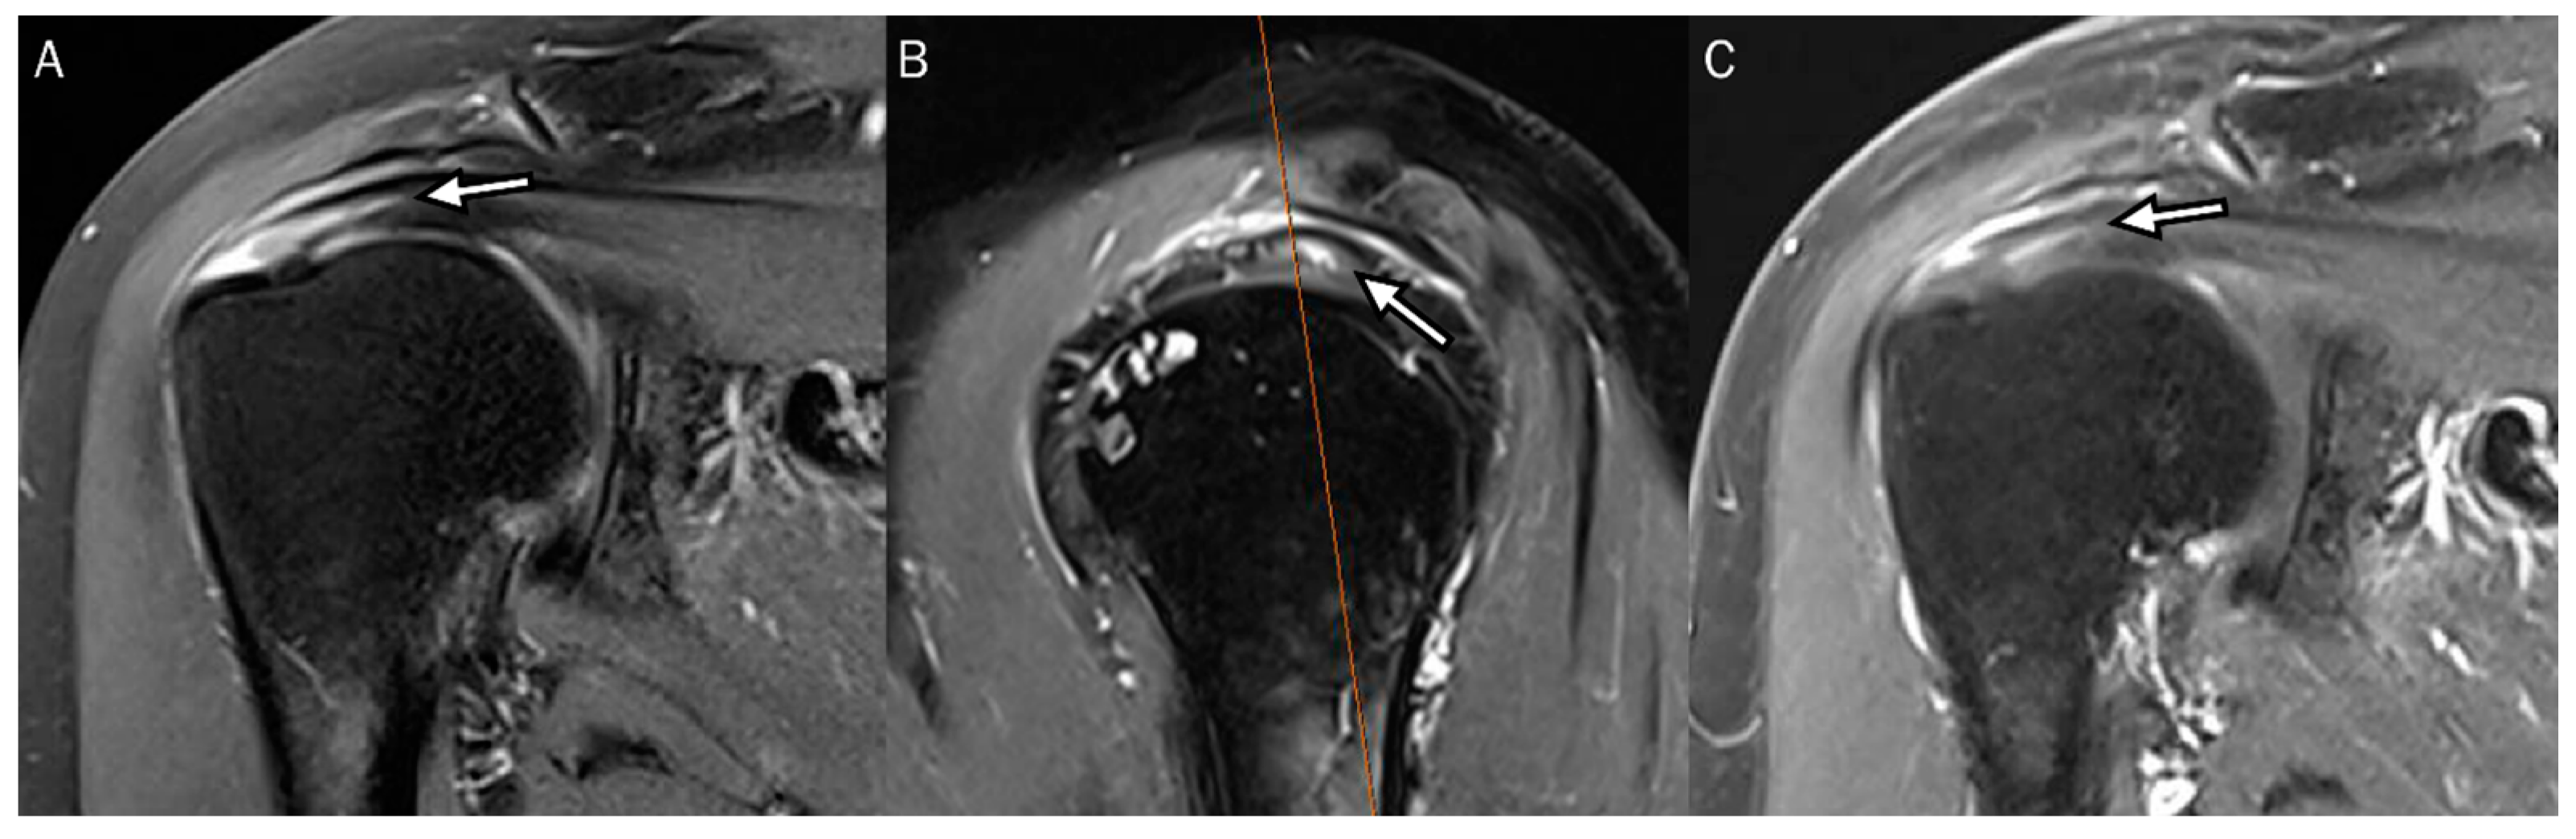

4. Radiologic Definition and Classification Using MRI

5. Radiologic Diagnosis of Delaminated Tears Using MRI